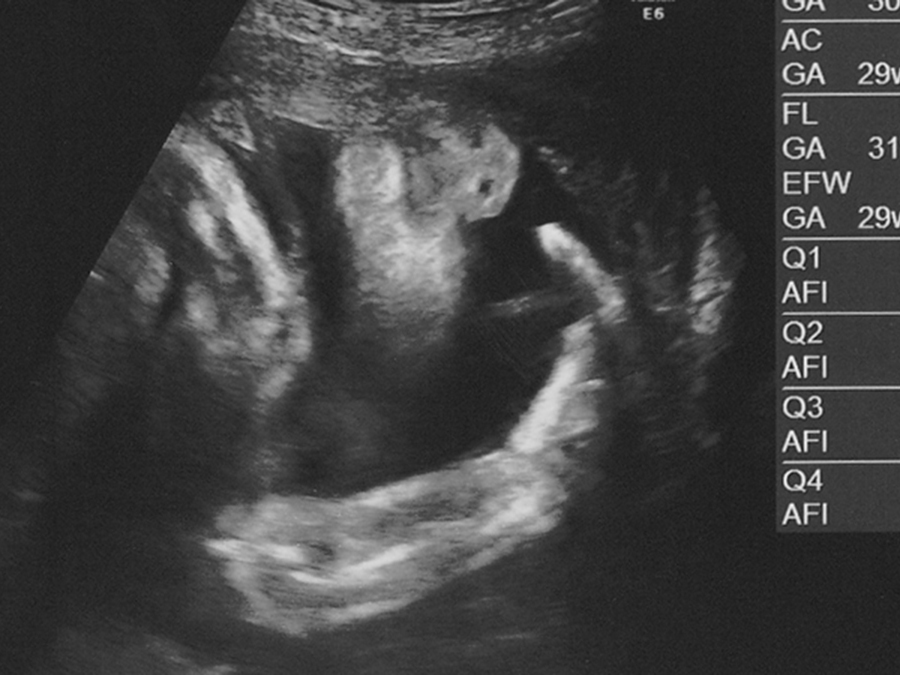

本来、お母さんのお腹の中で、赤ちゃんの頭は下になっており、お尻は上にあります。この状態を「頭位」と呼びます(下のイラスト)。

一方で、赤ちゃんのお尻が下にあり、頭が上になっている状態を「骨盤位」と呼び、この骨盤位の状態が一般的にいう「逆子」の状態です(下のイラスト)。